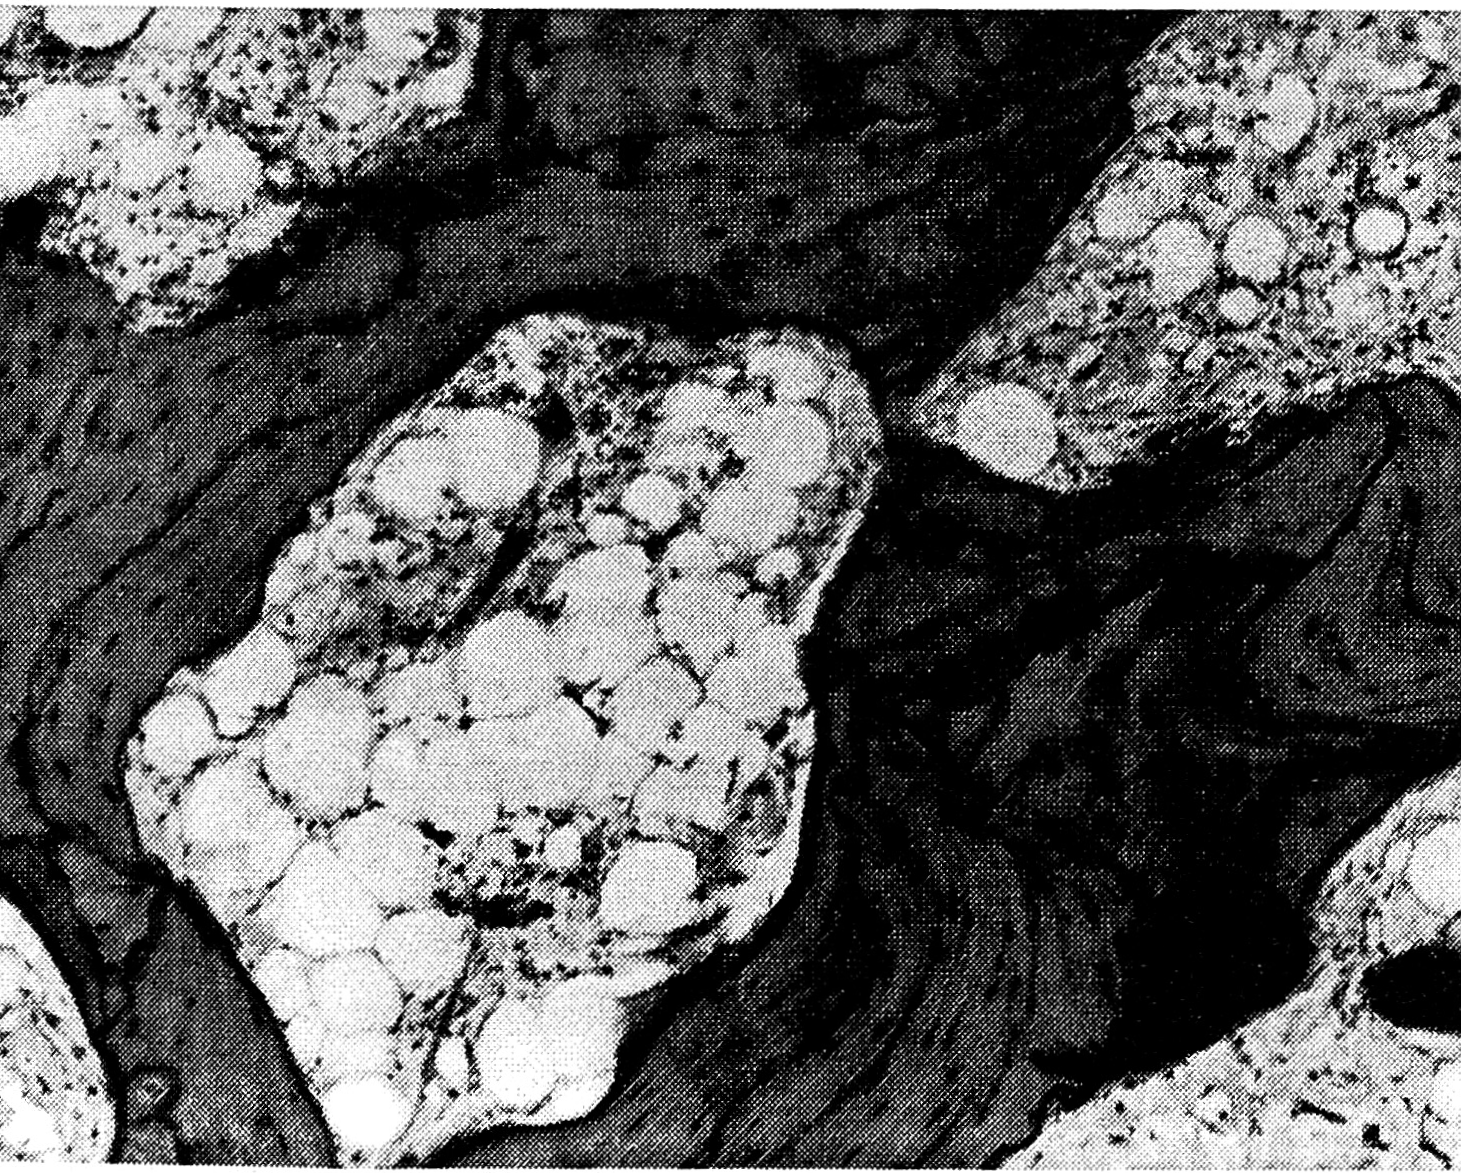

В отличие от активной фазы развития заболевания (стадии остеолиза и ремоделирования), в межтрабекулярных пространствах не выявляется клеточно-волокнистая ткань. Обычно она полностью замещена жировым костным мозгом (рис. 3) с незначительной примесью на отдельных участках кроветворного мозга. Значительно ослабевают признаки разрушения кости, что проявляется, в частности, в уменьшении числа остеокластов. Ослабевают и процессы остеогенеза. В этой стадии развития болезни Педжета редко обнаруживается формирование новых костных балок, лишь в некоторых участках встречаются явления аппозиционного остеогенеза на предсуществующей кости. Иными словами, в стадии затухания патологического процесса продолжают сохраняться отдельные признаки разрушения костной ткани и ее новообразования.

Рис. 3. В резко рарефицированной кортикальной кости межтрабекулярная клеточно-волокнистая ткань замещена жировым костным мозгом. III стадия заболевания.

Окраска гематоксилином и эозином. Ув. 100.

Необходимо отметить, что затухание активности патологического процесса происходит по направлению от эндоста к периосту компактной кости. Это проявляется в том, что клеточно-волокнистая ткань, содержащая функционально активные клеточные элементы, в том числе остеокласты, постепенно замещается жировым костным мозгом по направлению от эндоста к периосту.

В стадии затухания болезни Педжета уменьшается число сосудистых элементов. В участках, где процессы разрушения кости и остеоиндукции не обнаруживаются, а клеточно-волокнистая ткань замещена жировым костным мозгом, сосудистые элементы единичны, просветы их сужены.